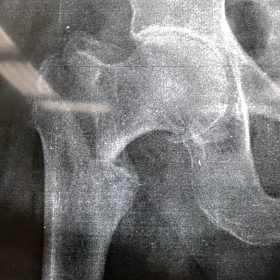

Υποκεφαλικό : Είναι ενδαρθρικό κάταγμα στον αυχένα του μηριαίου (το εσωτερικό του αρθρικού θυλάκου), το οποίο διακόπτει την αιμάτωση της κεφαλής του μηριαίου και οδηγεί σε μη πόρωση του κατάγματος (ΟΣΤΕΟΝΕΚΡΩΣΗ της Μηριαίας κεφαλής). Σε ασθενείς κάτω των 65 ετών αντιμετωπίζεται χειρουργικά με κοχλίωση στις πρώτες 12 ώρες. Τρείς βίδες σε σχήμα Τ με την βοήθεια τηλεόρασης διαδερμικά χωρίς διάνοιξη. Σε ασθενείς από 65-75 ετών γίνεται ολική αρθροπλαστική και σε ασθενείς άνω των 75 ετών αλλάζεται μόνο η κεφαλή χωρίς την αλλαγή της κοτύλης. Ο ασθενής περπατάει άμεσα μετεγχειρητικά στις 5 ώρες και εξέρχεται από το νοσοκομείο σε 1 -2 ημέρες. Στην κοχλίωση μπορεί να εξέλθει και την ίδια ημέρα.